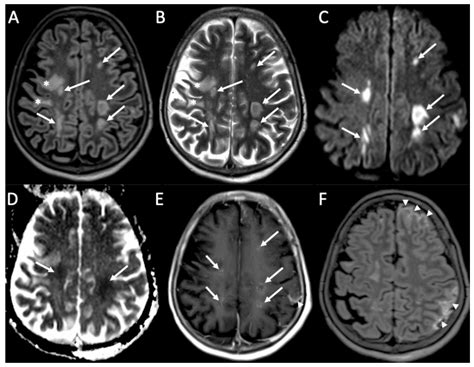

Diagnosing encephalitis involves a combination of clinical evaluation, laboratory tests, and imaging studies. The diagnostic process typically includes:

• Imaging Studies: Magnetic resonance imaging (MRI) and computed tomography (CT) scans to visualize brain inflammation and rule out other conditions.

Diagnosing meningitis involves a combination of clinical evaluation, laboratory tests, and imaging studies. The diagnostic process typically includes:

• Imaging Studies: Magnetic resonance imaging (MRI) and computed tomography (CT) scans to visualize inflammation and rule out other conditions.